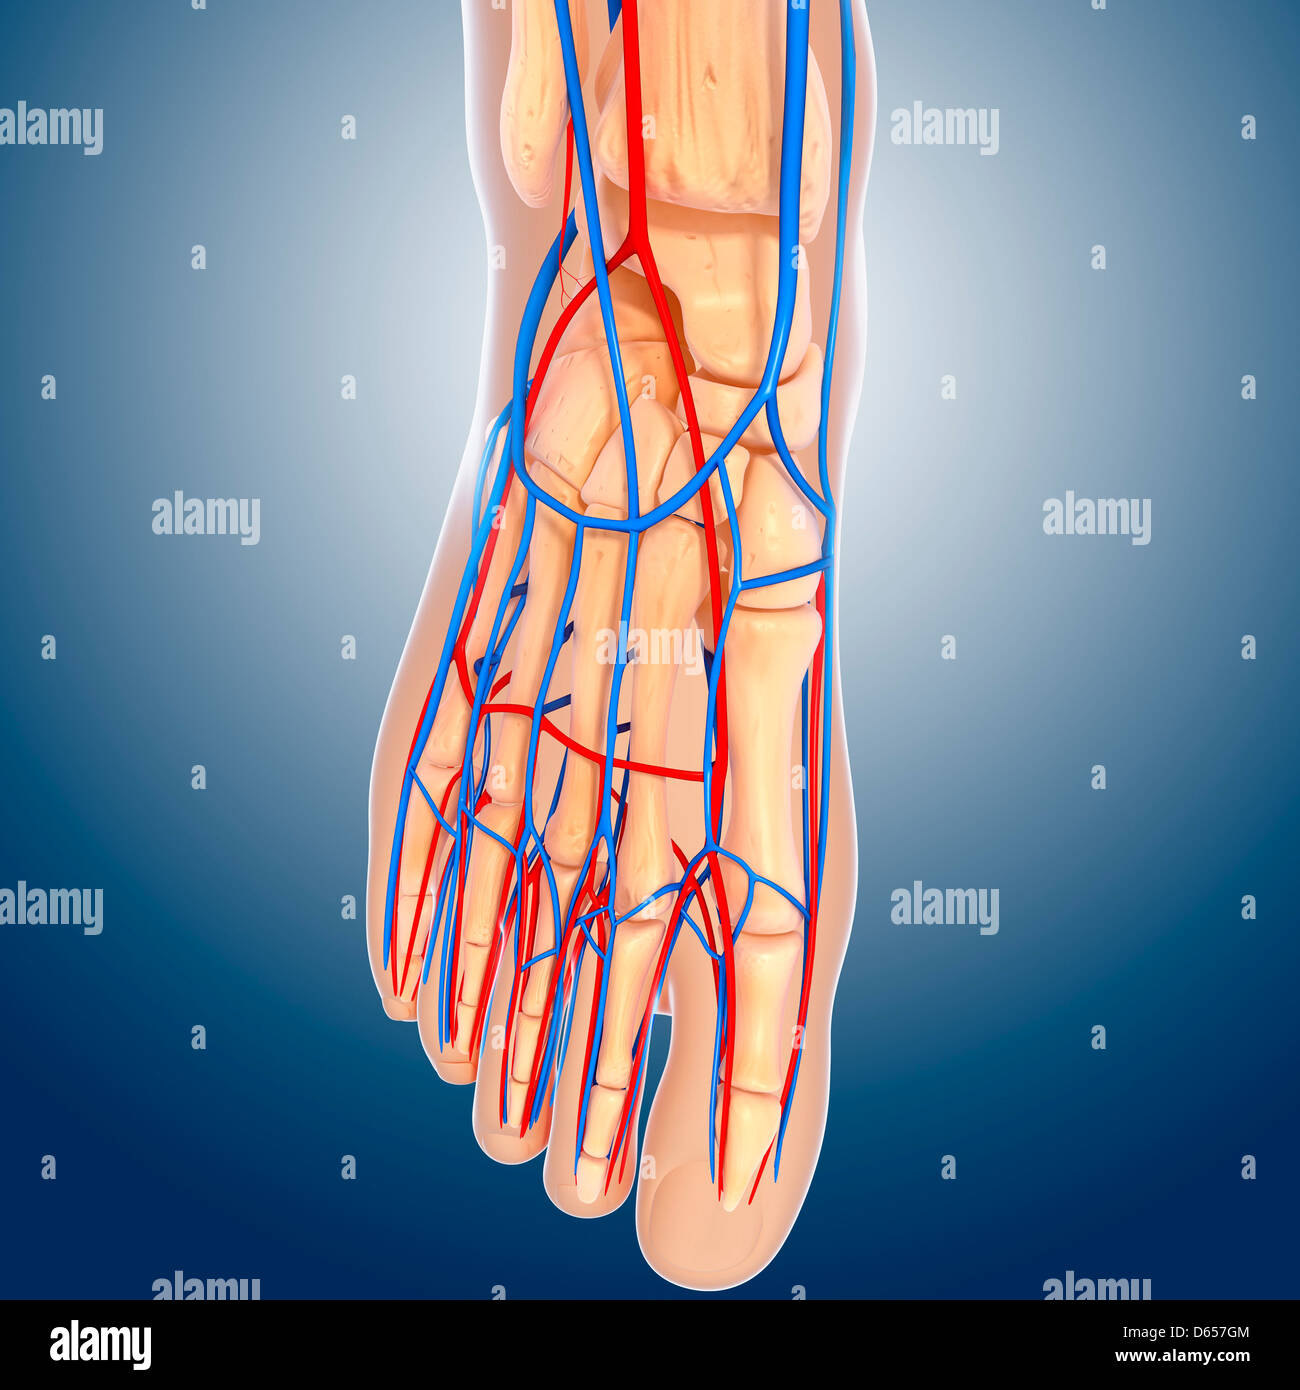

RF2ABM669–La médecine et les soins de l'illustre le tableau, les droits de l'anatomie du pied : Peau et tissus ectodermaux, os, muscles nerfs, vaisseaux sanguins